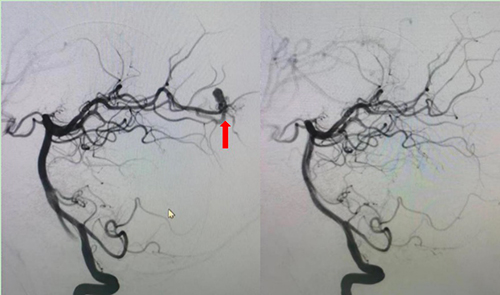

图2 右侧椎动脉造影图右图箭头处:畸形的血管团,左图箭头处:畸形血管团消失,拆雷成功

经过完善的术前沟通与准备,8月13日上午10时,这台“右侧大脑后动脉动静脉畸形栓塞术”正式开始,手术由吴荣昌医生主刀,郑铁华主任医师负责麻醉,杨雪护士长跟台。为进一步确保手术安全,吴荣昌医生邀请了天坛医院神经介入中心的刘恋主任指导手术。11时15分,手术顺利结束,术中造影显示小明博右侧大脑后动脉的畸形血管团被充分栓塞,藏在小明博颅内的这颗“雷”被顺利的拆除了。术后小明博没有发生偏盲、失明等并发症。术后6小时复查CT,小明博颅内血肿已经较前吸收,看到手术成功,家长悬着的心也终于放下了。